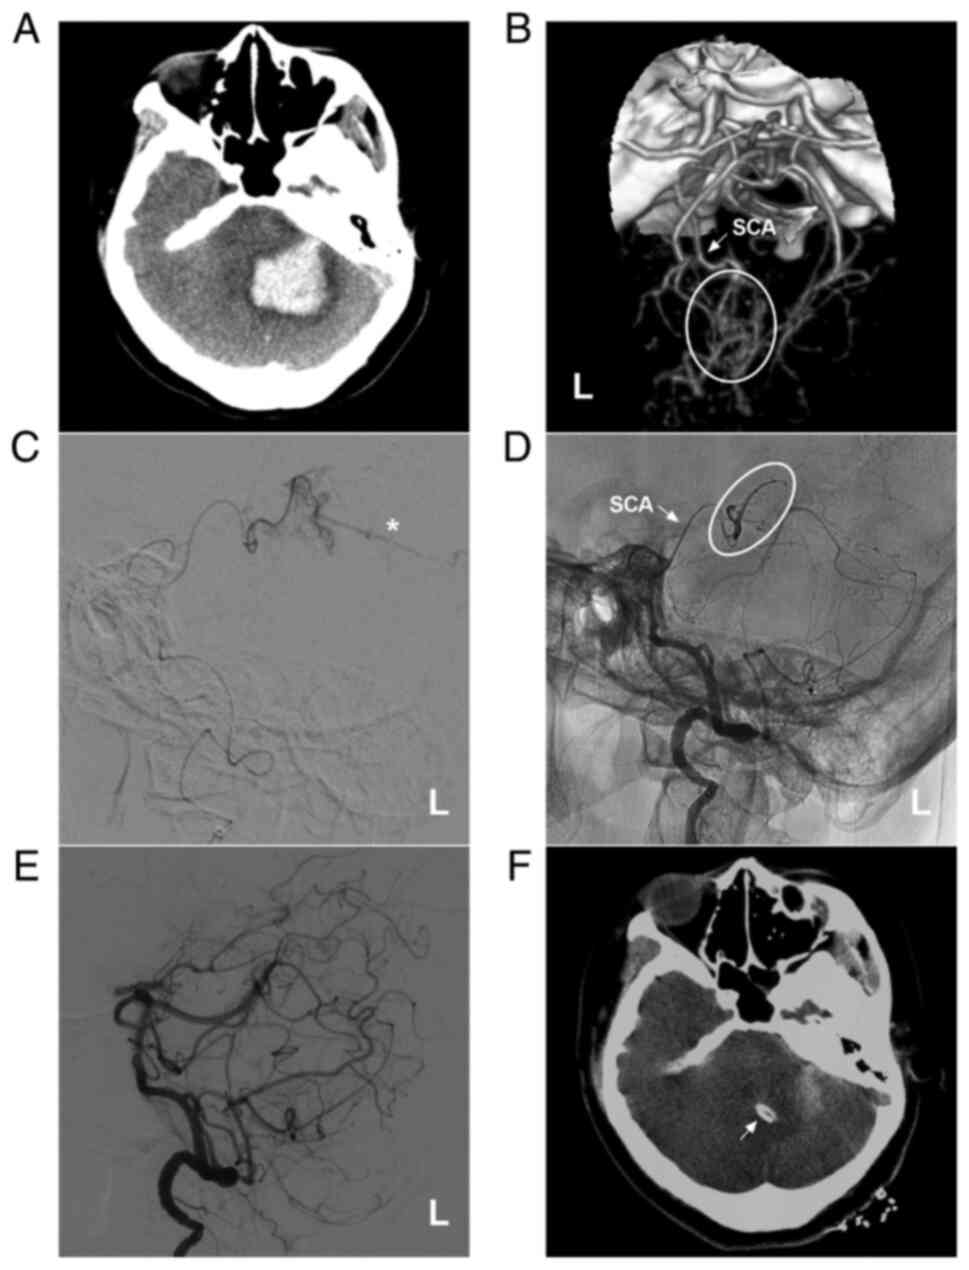

Figure 2

AVM located in the upper cerebellum with a mixed blood supply from the SCA, AICA and PICA. (A) Brain MRI showing a cerebellar vermis hemorrhage and the absence of flow voids beside the hematoma. (B and C) Lateral DSA of the left (B) and right (C) vertebral arteries showing that the AVM is widely supplied by the SCA, AICA and bilateral PICA and mainly drained by deep veins [in (B), the arrow noted the vein of Galen, and the triangle indicates the vein around the brainstem]. (D) X-ray showing the Onyx™ casting (square box) through the two branches of the SCA. (E) DSA of the left vertebral artery in the arterial phase after embolization showing that the volume of the AVM nidus decreased, and the stars denote the part of Onyx casting. (F) Post-operative CT scan showing an artifact (ellipse) of Onyx™. The case presented in this figure was a 17-year-old male who developed a sudden headache; he was awake after onset. EVT was performed. No EVT complication was observed. Currently, the boy is of normal health and attends university. However, further EVT was suggested. AICA, anterior inferior cerebellar artery; AVM, arteriovenous malformation; CT, computed tomography; DSA, digital subtraction angiography; L, left; MRI, magnetic resonance imaging, PICA, posterior inferior cerebellar artery; R, right; SCA, superior cerebellar artery.